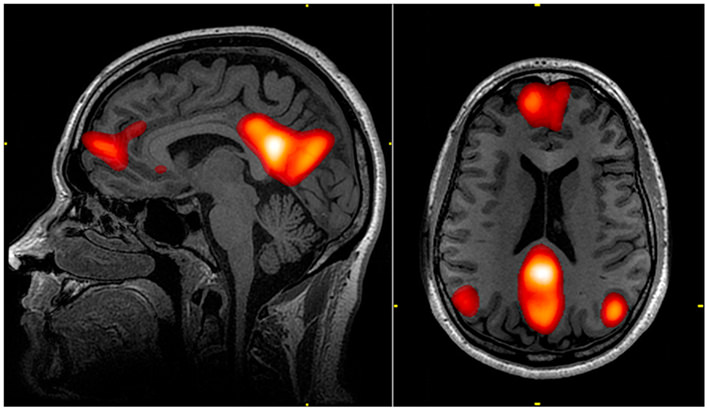

Why? Psychedelics does a good job of turning off the brains Default Mode Network (the ski hill).

The default mode network is a brain structure that connect the cortex to the areas involved with memory, emotion & self reflection.

When researchers imaged people's brains on psychedelics they found the default mode network to be suppressed.

Some reported that the ego is suppressed to a large extent because it resides in the default mode network.

It's as if your brain lets its walls down & start communicating.

Here’s an actual brain scan of someone on psychedelics (pic)

What you’re seeing is normally segregated regions of the brain starting to interact with each other.